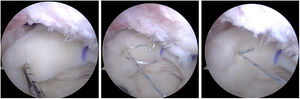

Se realizó una fijación periférica de menisco, en el siguiente orden: cuerno posterior con uso de sutura todo adentro (Fast Fix 360. Smith&Nephew, Londres-Reino Unido); fijación a capsula, lateral a tendón poplíteo, sin incorporación del mismo en los puntos. Usando los puntos de fijación meniscal hacia la periferia. Posterior, se fijó en periferia con Fast Fix 360, en tercio medio, puntos con técnica dentro fuera en tercio anterior (protector meniscal Arthrex. Naples, Florida, Estados Unidos). (Tomado de autores.).

Se confirma estabilidad y movilidad articular del aloinjerto cadavérico.